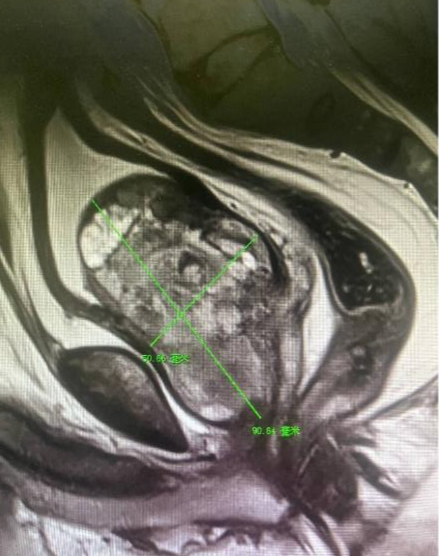

为解决排尿困难问题,两名患者均慕名前往延安市中医医院泌尿外科郭巍主任门诊求助。郭巍主任详细询问病史、完善相关检查后,给出了明确诊断——两人均为巨大体积前列腺增生。检查结果显示,张某的前列腺体积约221ml,是正常前列腺体积(约15ml)的15倍;李某的前列腺体积约186ml,是正常前列腺体积的12倍。